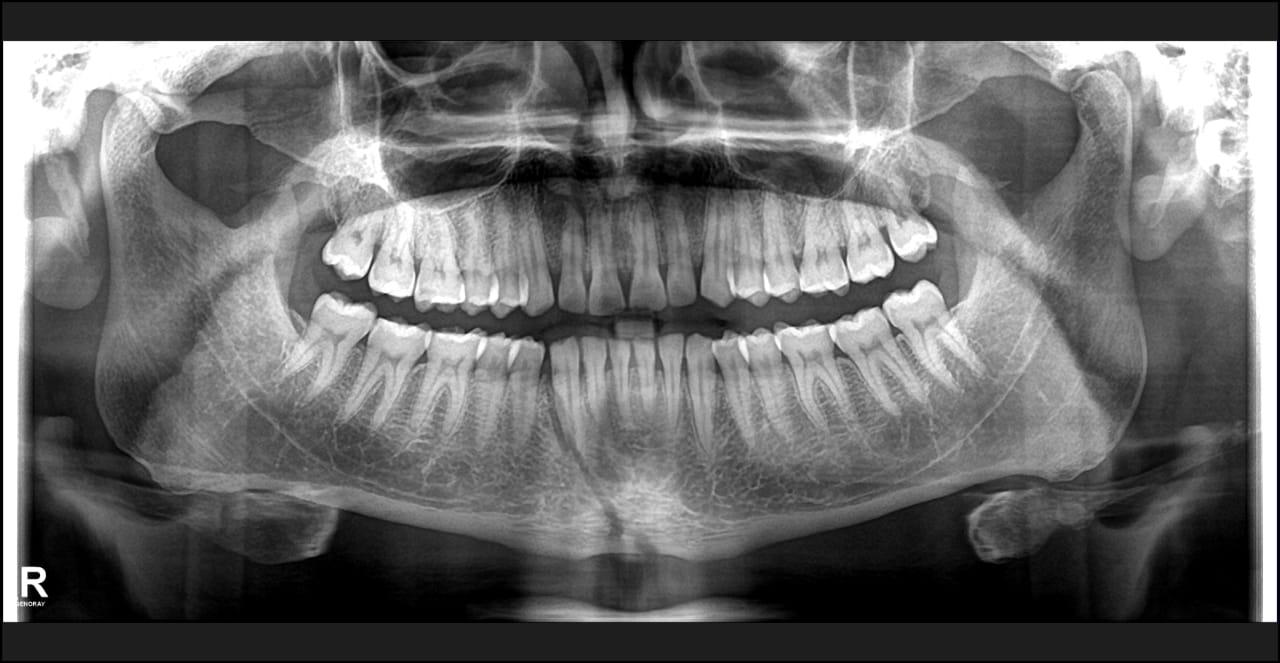

Case Scenario 6 - Fractured Mandible

33 year old male patient reported to our clinic with history of road traffic accident and severely bleeding wounds. Medical history suggested that his fit for the the dental procedure. Radiological examination was conducted with the help of opg. Local anaesthesia is administered and arch bar is placed in upper and lower jaw. the the occlusion is established at Centric occlusion . The Jaws were fixed to each other for 21 days. Post operative instructions were given that patient has to be on liquid diet for next 21 days as he won't be able to chew the food due to closure of mouth. The fractured segment treatment this is a very important step and 90% of fracture related to oral cavity are treated in the same conservative way.